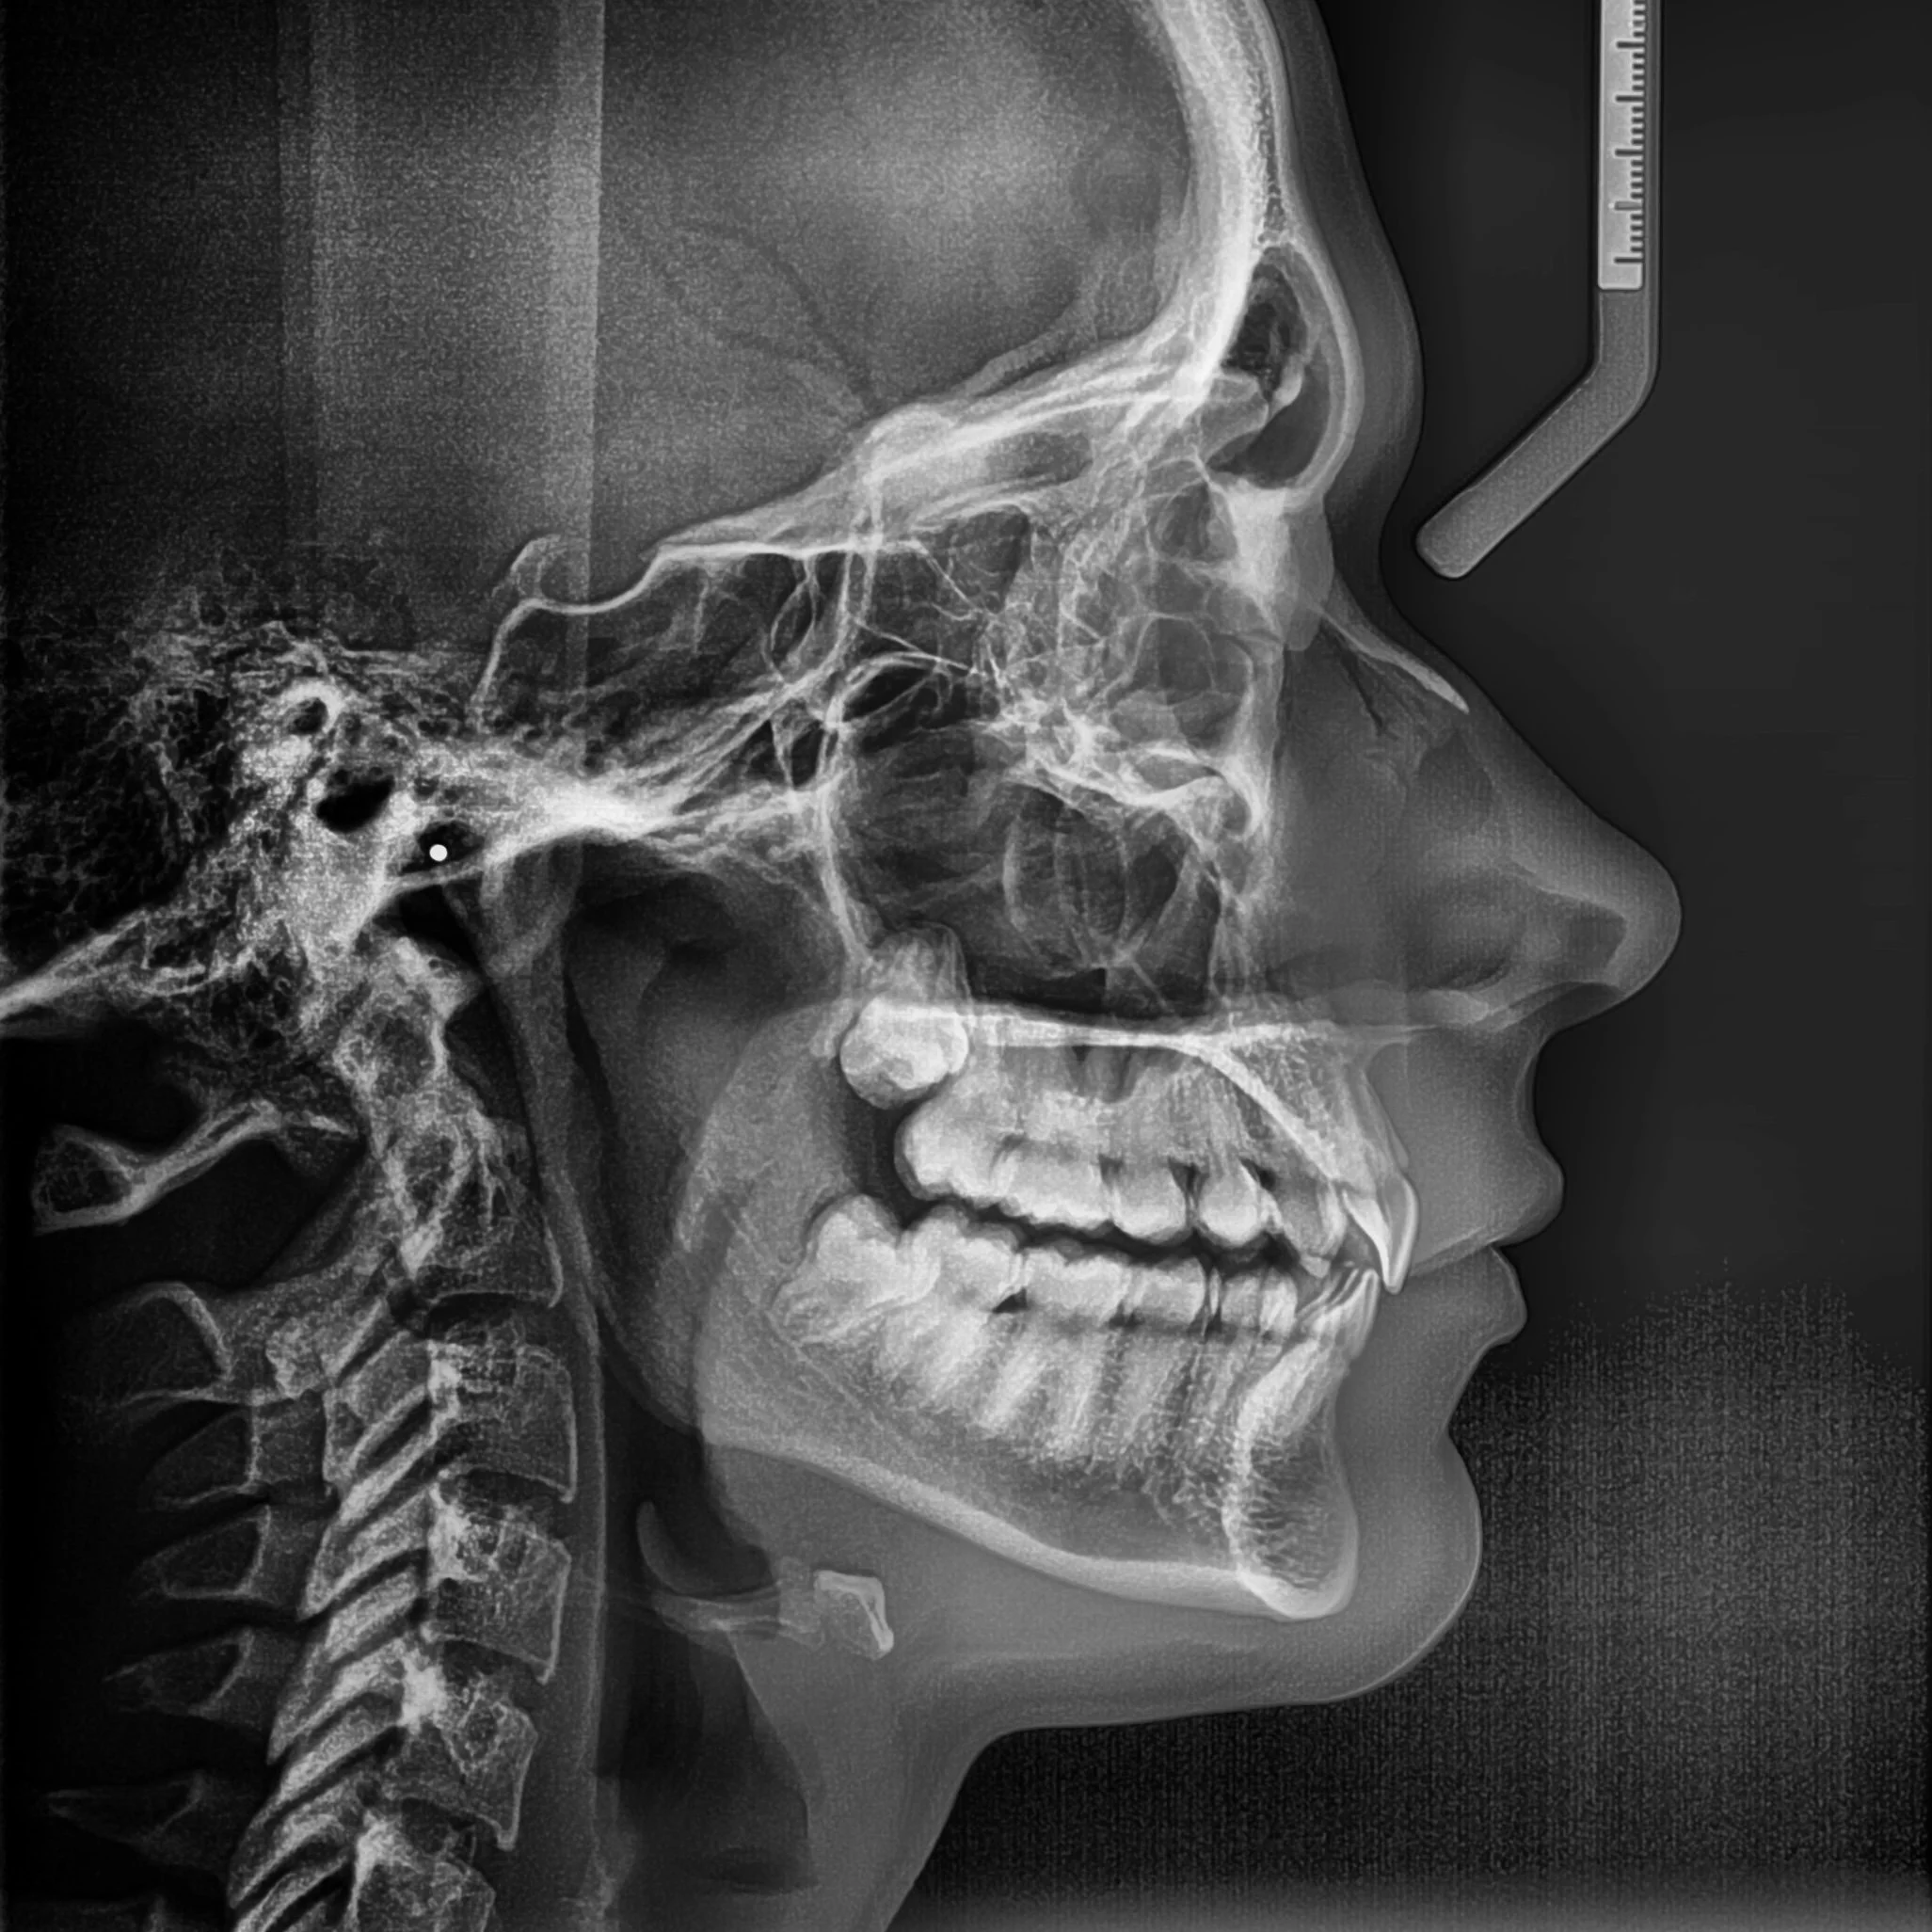

Reducimos el uso de RAYOS-X sin perder

PRECISIÓN

Con nuestros equipos podemos obtener imágenes panorámicas, de perfil y en 3 dimensiones con gran nitidez, gracias a su sistema innovador que sigue perfectamente la curva natural de tus dientes, consiguiendo ver toda tu boca de la forma más clara posible, enfocándonos solo en lo que realmente importa: diagnósticos mucho más precisos con la menor radiación necesaria.

Creemos que una buena imagen hace la diferencia. Por eso, somos un centro especializado en radiología dental y diagnóstico por imágenes, enfocado en ofrecer estudios precisos, confiables y de alta calidad, que respalden una correcta toma de decisiones clínicas. Trabajamos con tecnología de última generación y protocolos cuidadosamente establecidos para garantizar imágenes nítidas, seguras y consistentes en cada estudio.